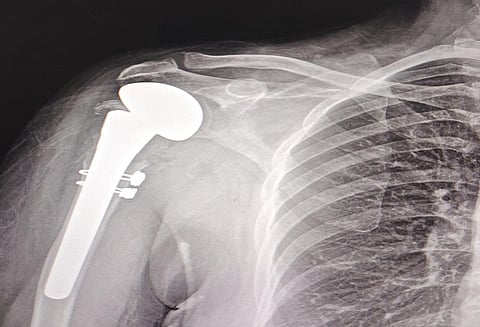

نجح فريق جراحي متخصص بمدينة الملك سلمان بن عبدالعزيز الطبية بالمدينة المنورة، في إجراء عملية دقيقة لاستبدال رأس عظمة العضد وتركيب مفصل صناعي للكتف، لمستفيدة في العقد الخامس من عمرها كانت تعاني من كسر متفتت في رأس عظمة العضد وقطع في الأربطة الدوارة لمفصل الكتف الأيسر.

وأوضح تجمع المدينة المنورة الصحي بأن المستفيدة خضعت لفحوصات دقيقة شملت الأشعة السينية والمقطعية لتحديد مدى الإصابة وخطة التدخل الجراحي الأنسب، وبعد دراسة الحالة الصحية مع الفريق الطبي تقرر إجراء الجراحة التي تضمنت استبدال عظمة العضد بمفصل صناعي مع إعادة بناء الأربطة للكتف من خلال تدخل جراحي ونوعي.

وبين تجمع المدينة المنورة الصحي أن العملية تكللت بالنجاح ولله الحمد وأكملت المستفيدة برنامج تأهيلي شامل بإشراف قسم العلاج الطبيعي، وأظهرت استجابة إيجابية وتحسنًا في حركة المفصل، وغادرت المستشفى بصحة جيدة .